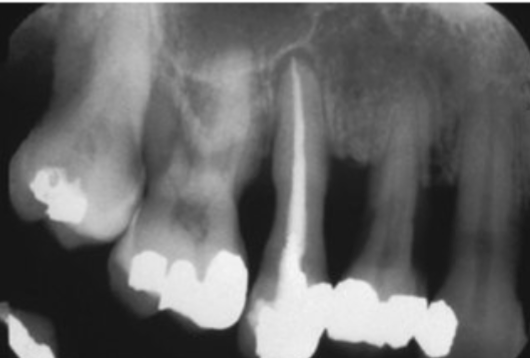

<p>Functions of Alveolar Bone:</p>

Functions of Alveolar Bone:

• alveolar bone protects roots of teeth by forming bony sockets that provide support

• constantly undergoes periods of bone remodeling when teeth are subject to mechanical forces

• comprised of mineralized connective tissue formed by osteoblasts

• least stable part of periodontium because of constant osteoclastic/osteoblastic action

<p>Two Major Cell Types:</p>

Two Major Cell Types:

• osteoblastss which produce the bone matrix of collagen fibers and other protein fibers

• osteoclasts which are cells that remove mineral material and organic matrix of bone

Characteristics of the Alveolar Bone:

• extracellular matrix contains-collagen fibers and gel-like substances-major component

• bone matrix is rigid because of mineral deposition of calcium and phosphate-subsequently transformed into hydroxyapatite

• alveolar bone contains-blood vessels and nerve innervation